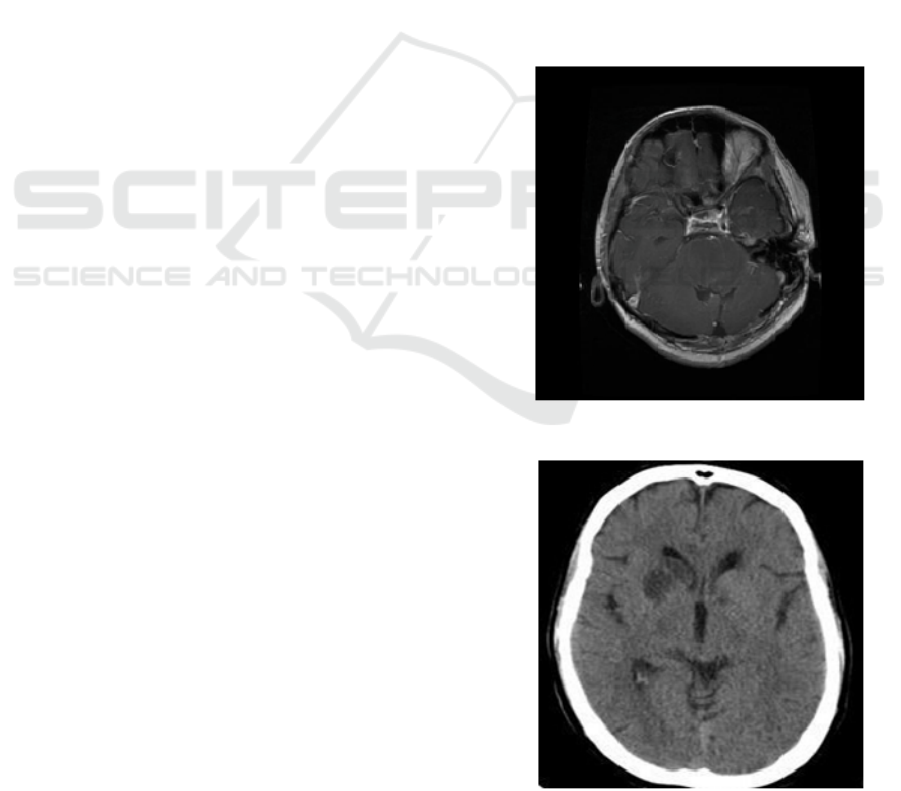

There are two types of datasets taken for this

work, testing and training. Each dataset consists of

cancer and non-cancer MRI scans of brain. Fig. 1

shows one of the training MRI scans of the cancer

cells belonging to the tumor called glioma.

Figure 1: MRI scan of brain consistingglioma

Figure 2: MRI scan of benign cells

The Fig. 2 shows one of the training MRI scans

of benign cells (non-cancer cells).